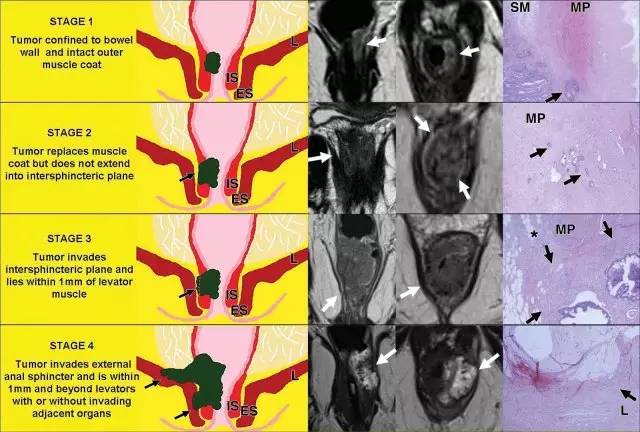

肛门复合体 - 括约肌和直肠肌

肛管直肠结合部,直肠固有肌层变化:1. 环形肌变厚形成内括约肌。2. 外括约肌复合体由肛提肌最下部,耻骨直肠肌和外括约肌组成。3. 低位肛管中两个括约肌形成明显的括约肌间隙。

低直肠肿瘤与阳性切缘率较高,局部复发率高,存活率差相关。这主要是由于解剖学考虑以及直肠系膜在此水平降落的事实。

有学者提出了一种低直肠肿瘤 T 分期。这种分期是基于冠状和轴向 T2 加权图像。

针对低直肠肿瘤,可以根据肿瘤分期进行三种不同的手术方式。

图 23 手术方式。黑色线:TME;绿色线:ISR;灰色线:ELAPE

「T」和「A」其实都应该是被归为 T 分期,「T」为肛提肌水平以上直肠的 T 分期,「A」为肛提肌水平以下直肠肛管的 T 分期。

该点评其实道出了低位直肠癌的精䯝,再次附上中高位和低位直肠癌分期: